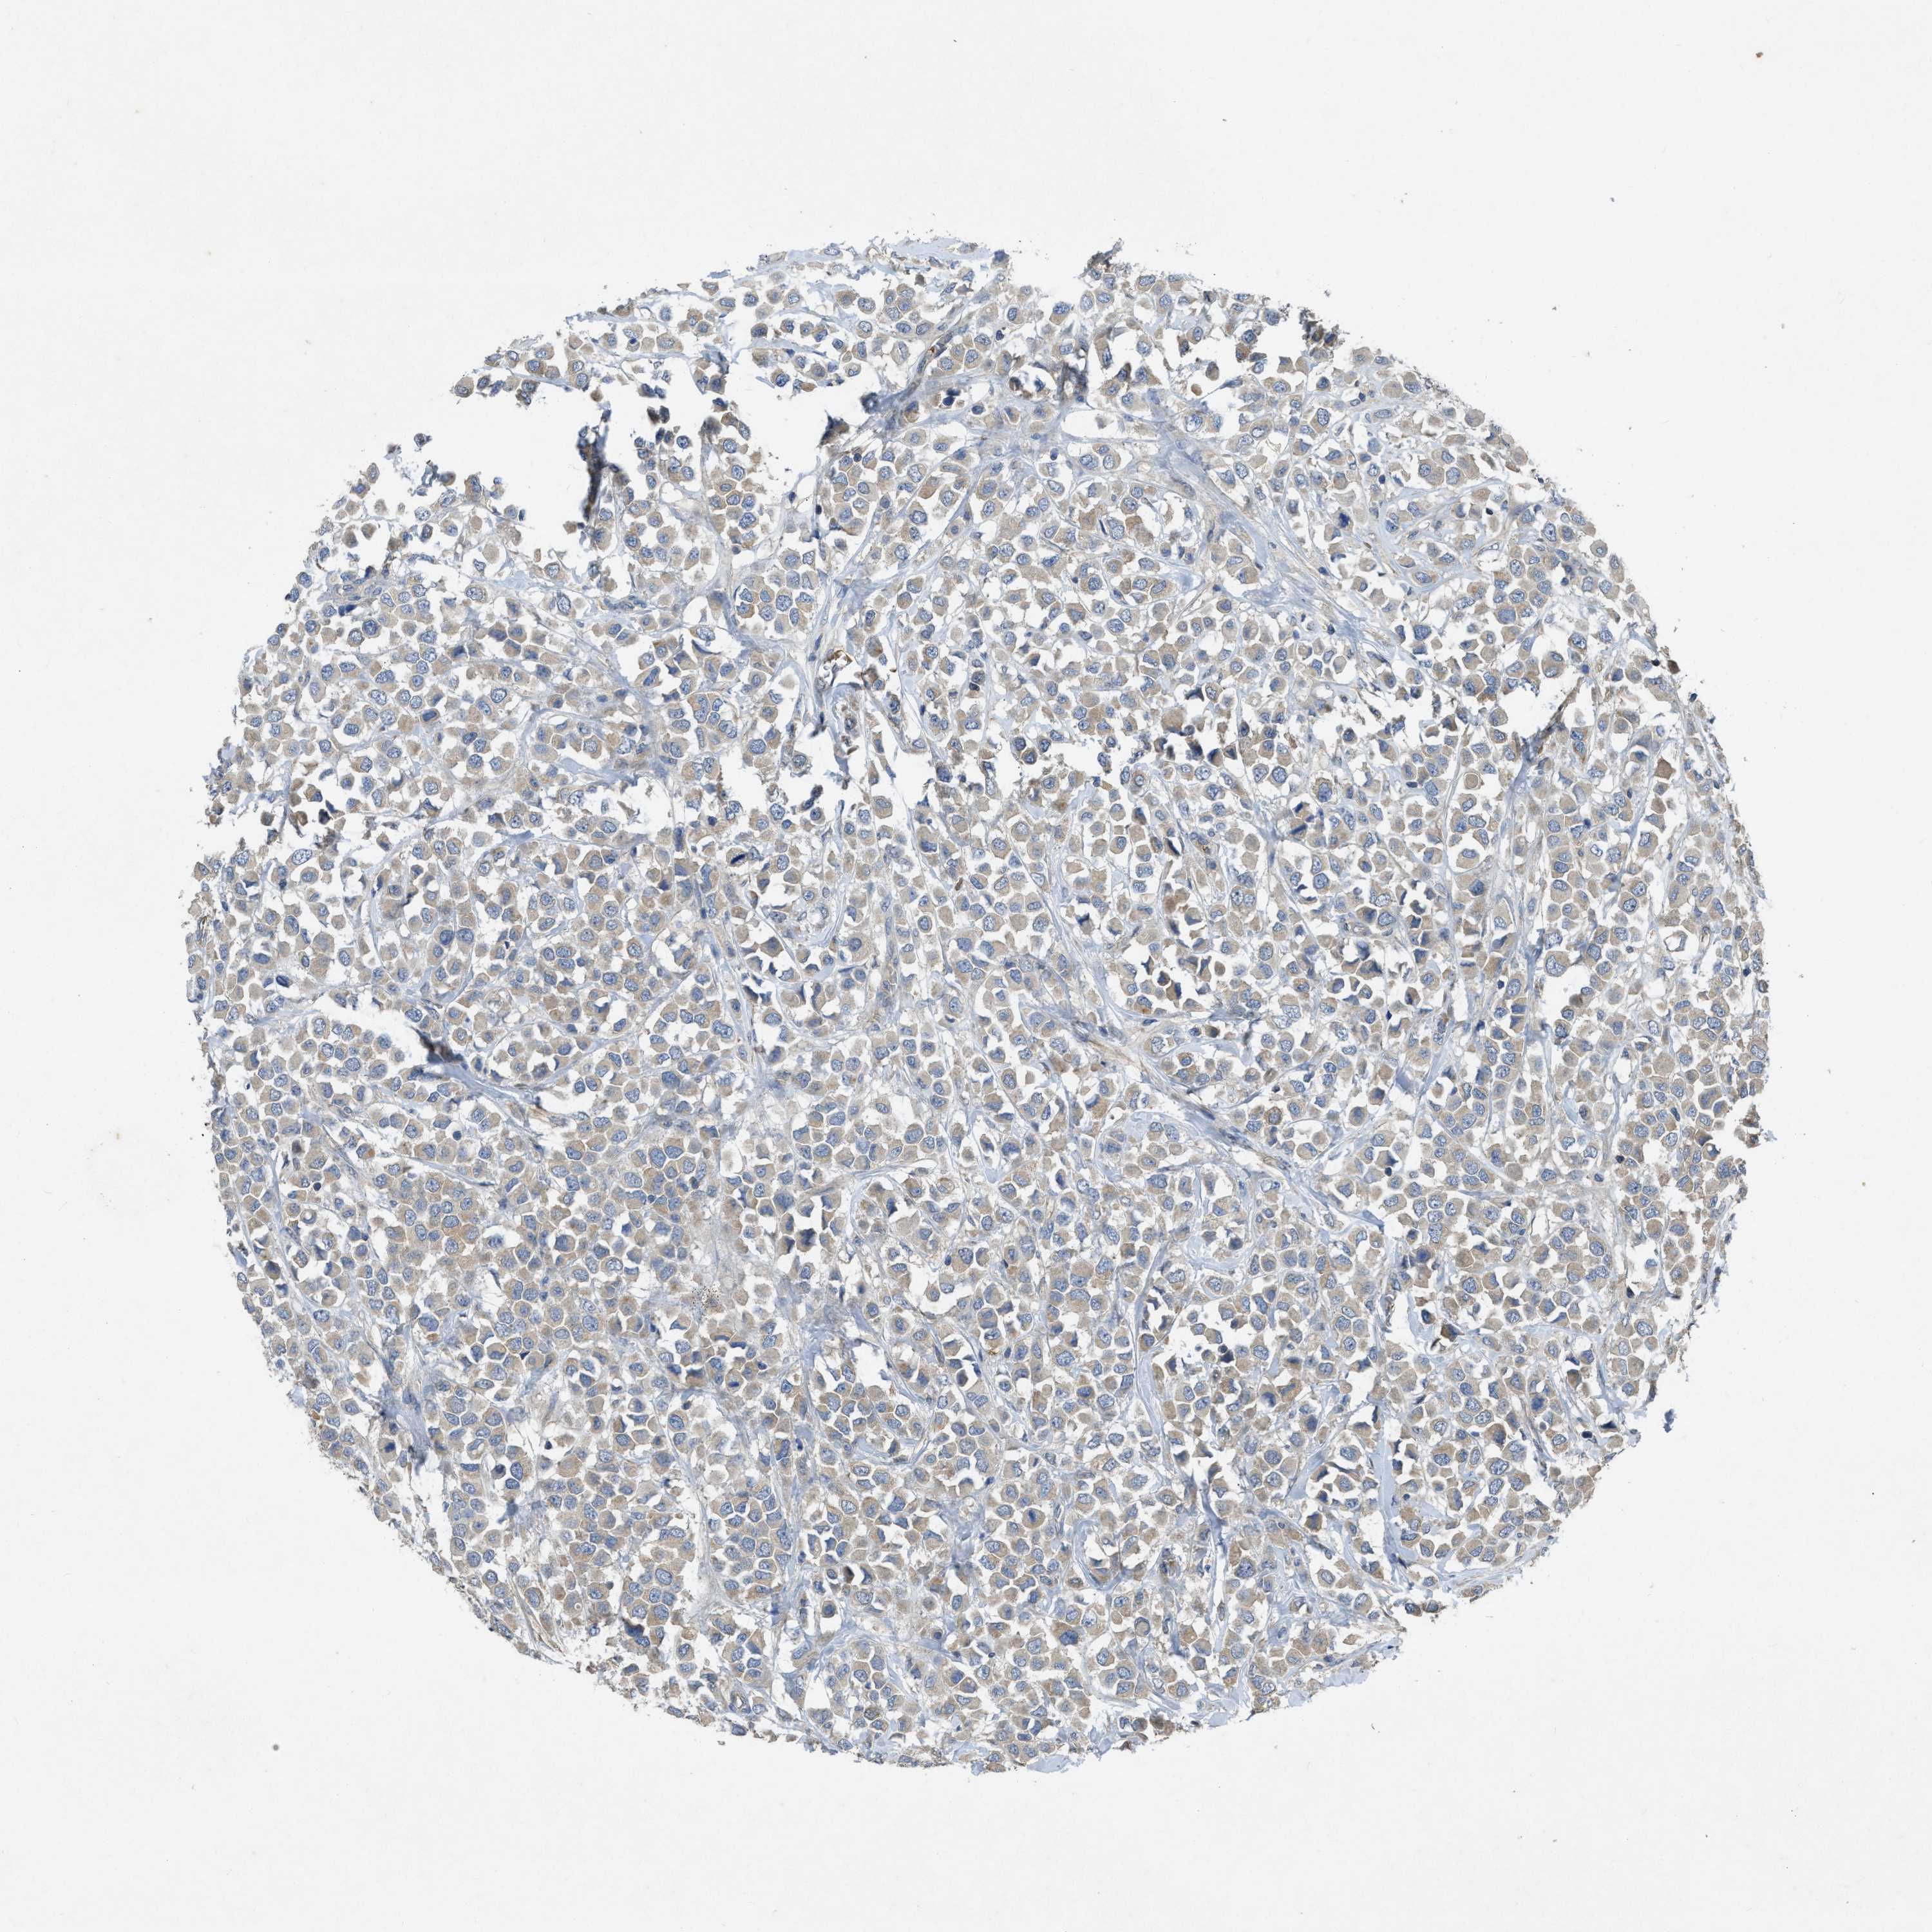

CANCER BREAST CANCER Show tissue menu

BRCA TCGA BRCA VALIDATION PROTEIN EXPRESSION

Breast cancer

Human cancer

Breast invasive carcinoma